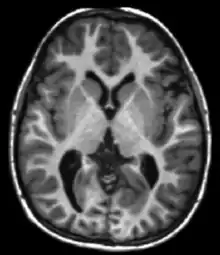

Apparent diffusion coefficientADCReduced T2 weighting by taking multiple conventional DWI images with different DWI weighting, and the change corresponds to diffusion.[28] Low signal minutes after cerebral infarction (pictured).[29]